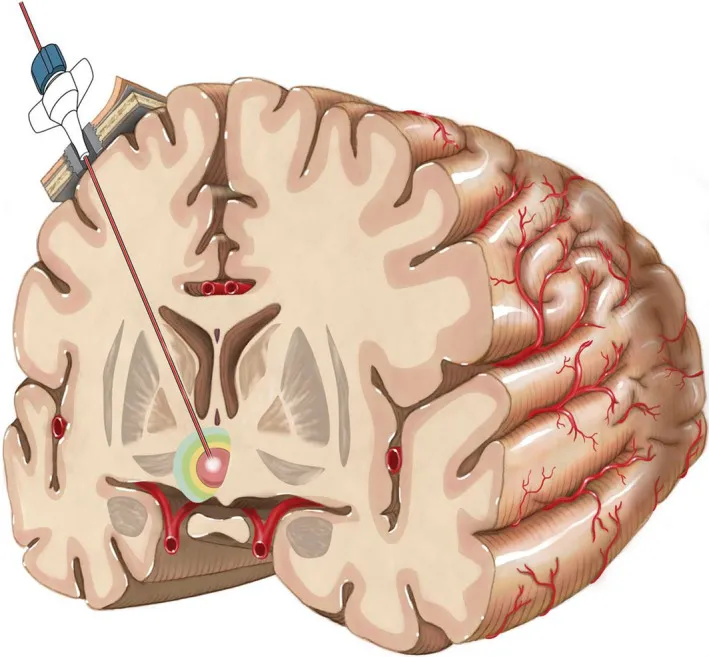

磁共振MRI引导的激光间质热疗(LITT)使用立体定向技术,可以将纤细的激光光纤直接植入颅内病灶的核心,并使用激光热能破坏病灶,达到类似于手术切除的效果。

LITT 2-4mm的切口旨在造成最小的组织破坏,只需将可释放激光的探针深入脑部即可消融致痫灶,因此只需要一次缝合,也不需要重新打开先前的硬膜闭合,减轻了开颅手术为患者带来的身心压力,同时避免了伤口裂开、脑脊液泄漏和感染等固有风险。

将激光探针通过使用不同立体定向或导航平台的固定螺栓插入目标区域。图为下丘脑错构瘤的治疗方法展示

Rutka教授还在论文中称,LITT技术已在其临床中被广泛运用,并不断被更多患者接受。这项技术利用了三个关键要素:

(1)立体定向方法,将激光探针精确定位在治疗目标内;

(2)手术激光系统随时间变化的热组织消融;

(3)MRI热像仪可实时监测温度变化和组织破坏。

在手术过程中,实时MRI会生成患者大脑的实时温度图。这使外科医生能够连续监测脑组织温度,确保激光诱导的损伤有效地靶向病灶,而不受周围健康组织的限制。